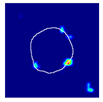

| True label: Crescentic |  |  |  |  |  |

| single-multiclass: Crescentic p = 0.999, IoU = 0.154 | |||||

| multiple-binary: Crescentic p = 1.000, IoU = 0.128 | |||||

| Spatially guided: Crescentic p = 0.979, IoU = 0.740 | |||||